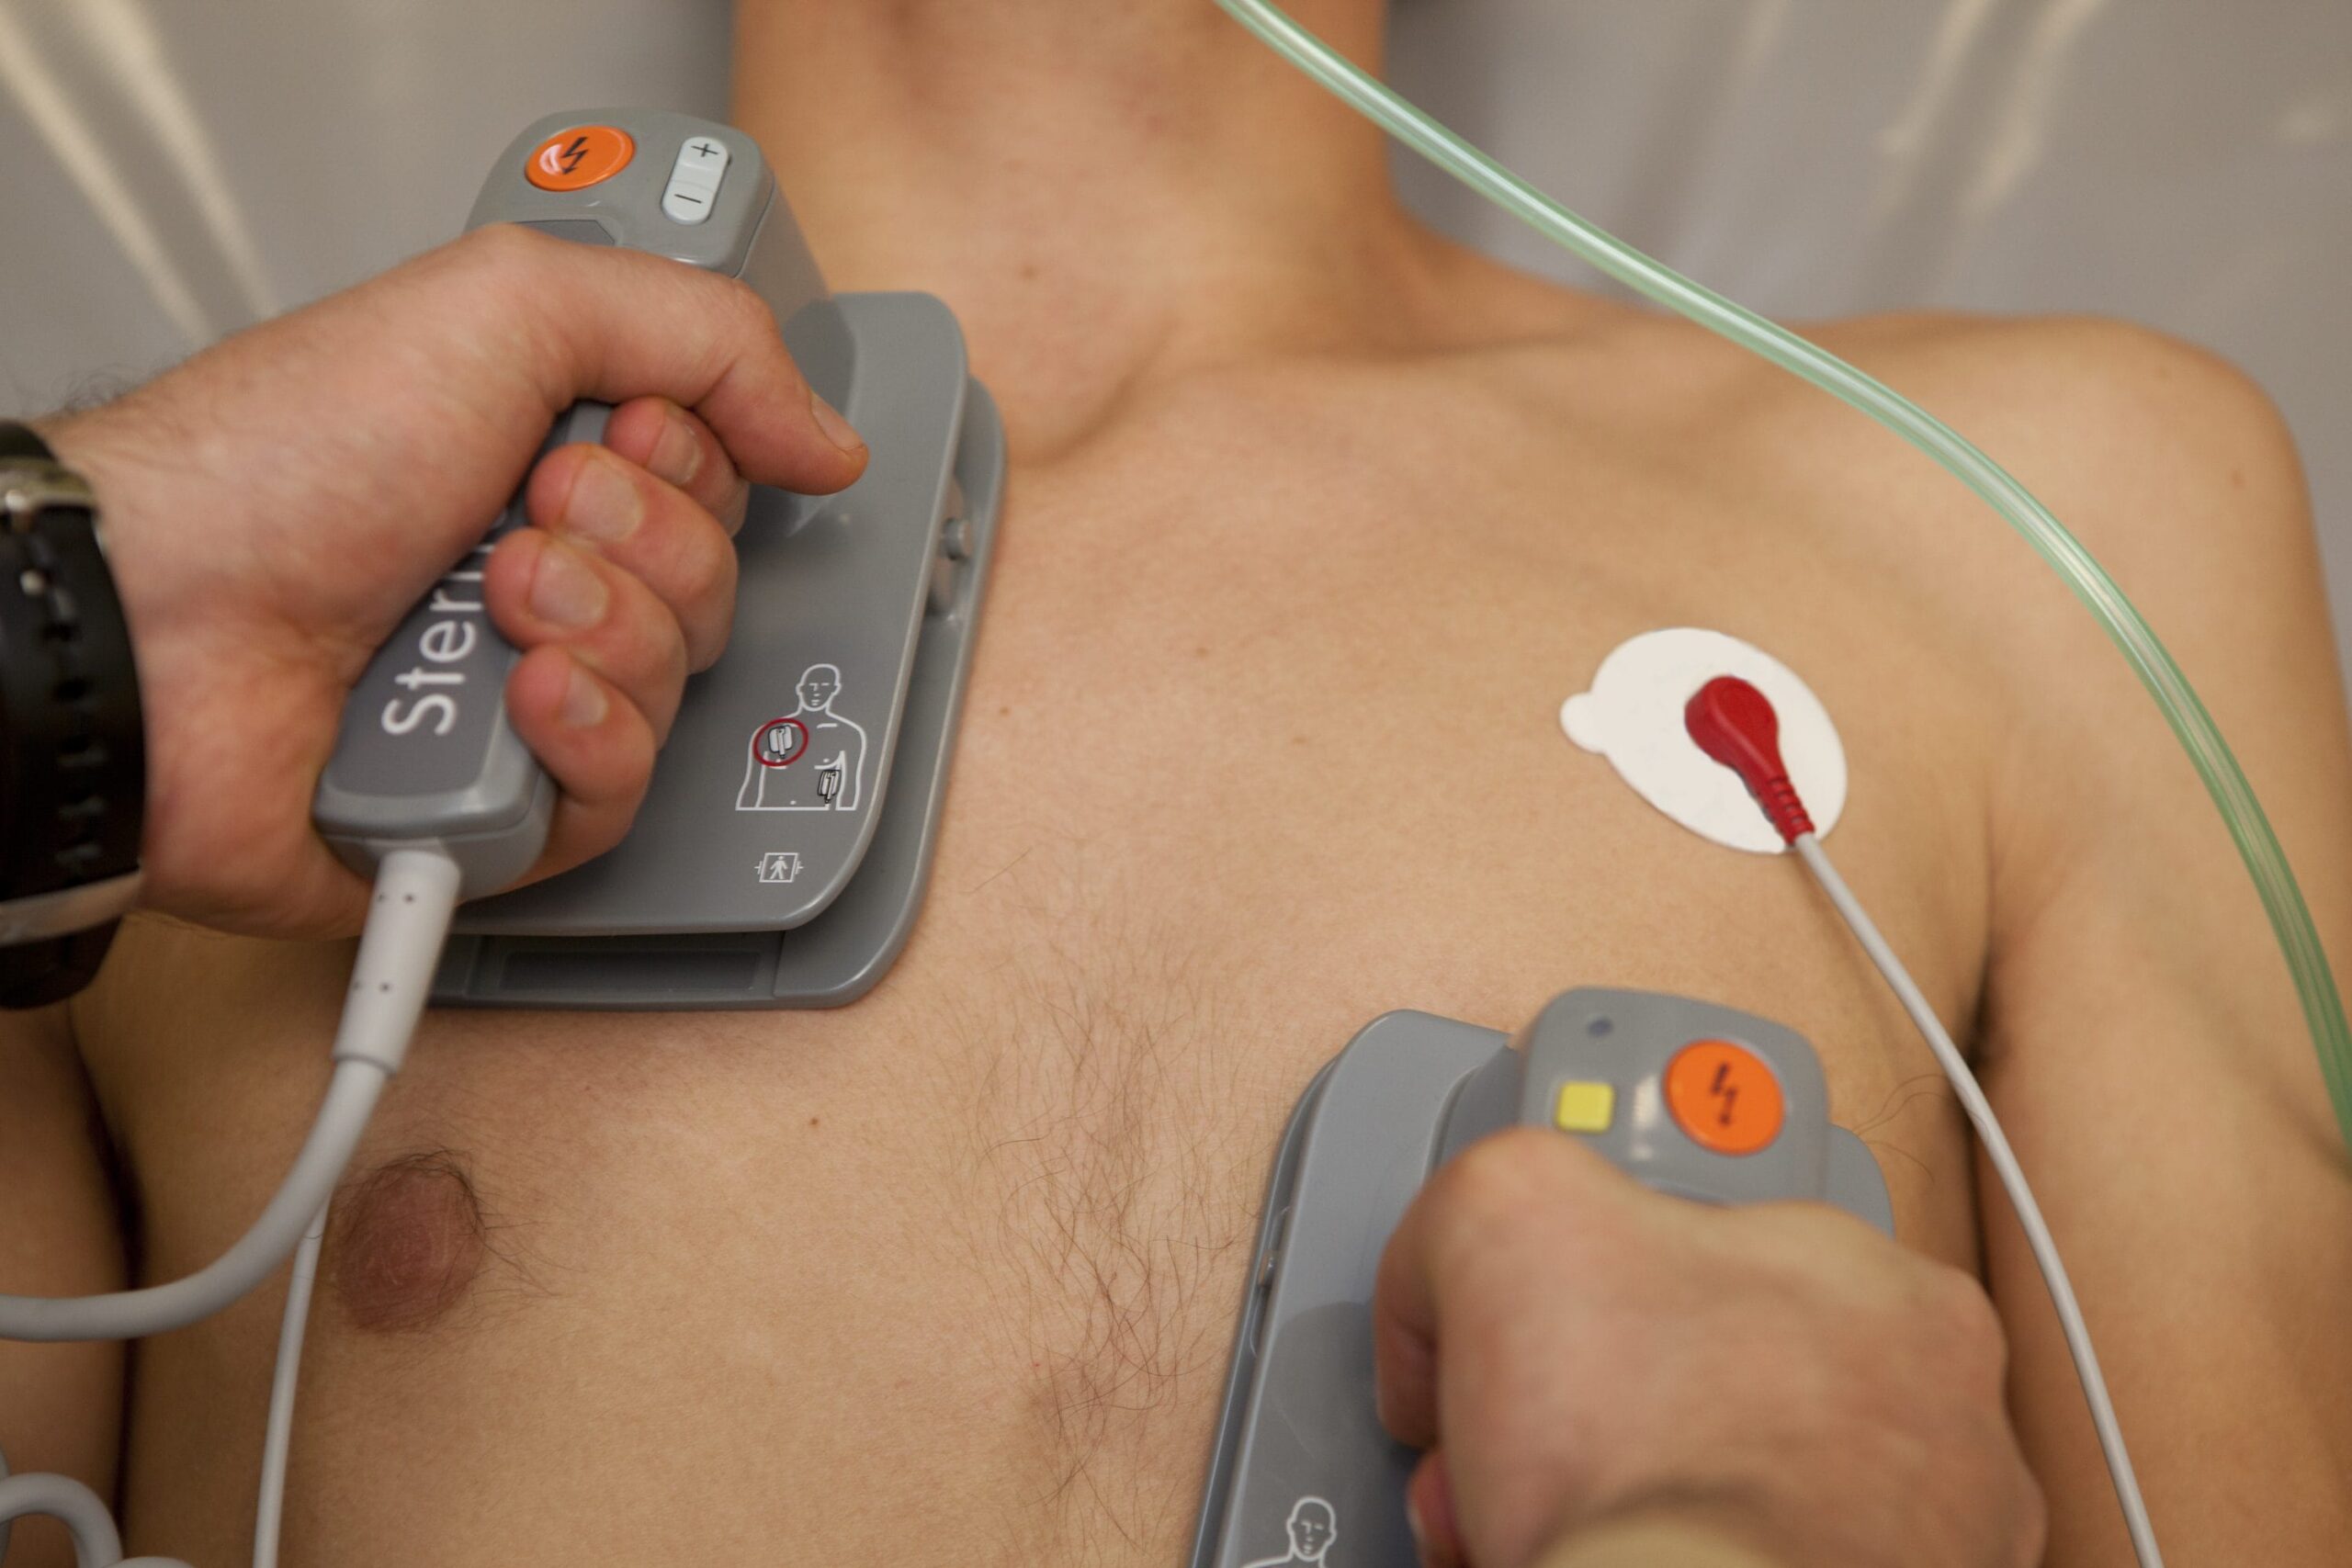

Fordi hjertestarteren brukes og hvordan den fungerer

Defibrillatoren spiller inn i nærvær av alvorlige uregelmessigheter i hjerterytmen. I disse tilfellene en Last ned målrettet strøm Han kan «tilbakestille» hjerterytmen. Den elektriske utslippet depolariserer alle hjertemuskelceller samtidig, slik at hjertet kan «starte på nytt» med riktig hjertrytme. Hver hjertestarter er utstyrt med to limplakk som skal påføres på brystet. Disse tillater å overvåke hjerteaktivitet og oppdage eventuelle arytmier. Når problemet er identifisert, er kraften til utslippet satt og platene aktiveres. Manuelle hjertestartere krever inngripen av kvalifisert personell, i stand til å tolke EKG og doser utslippet riktig. I dag er det imidlertid Semi-automatiske hjertestartere (DAE). Disse oppdager uavhengig arytmi, setter energien og administrerer utslippet uavhengig, og ber bare om riktig anvendelse av platene.

Defibrillering blir ofte fulgt av Kardiopulmonal gjenopplivning (RCP). Når hjertet stopper, stoppes også strømmen av blod oksygenert til de vitale organene, først og fremst, først og fremst. RCP tjener til å opprettholde en minimal sirkulasjon til restaureringen av takten.